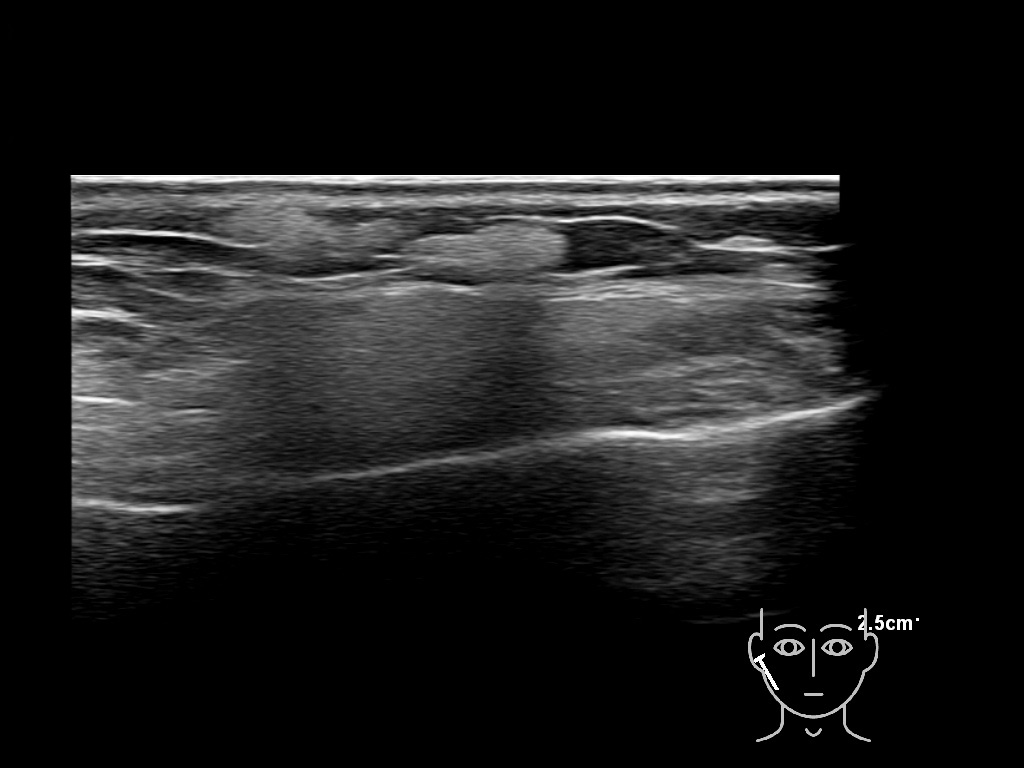

Fillers

Draw in the second image below where the fillers are located. To check if your answer is correct, swipe the first image to the right.